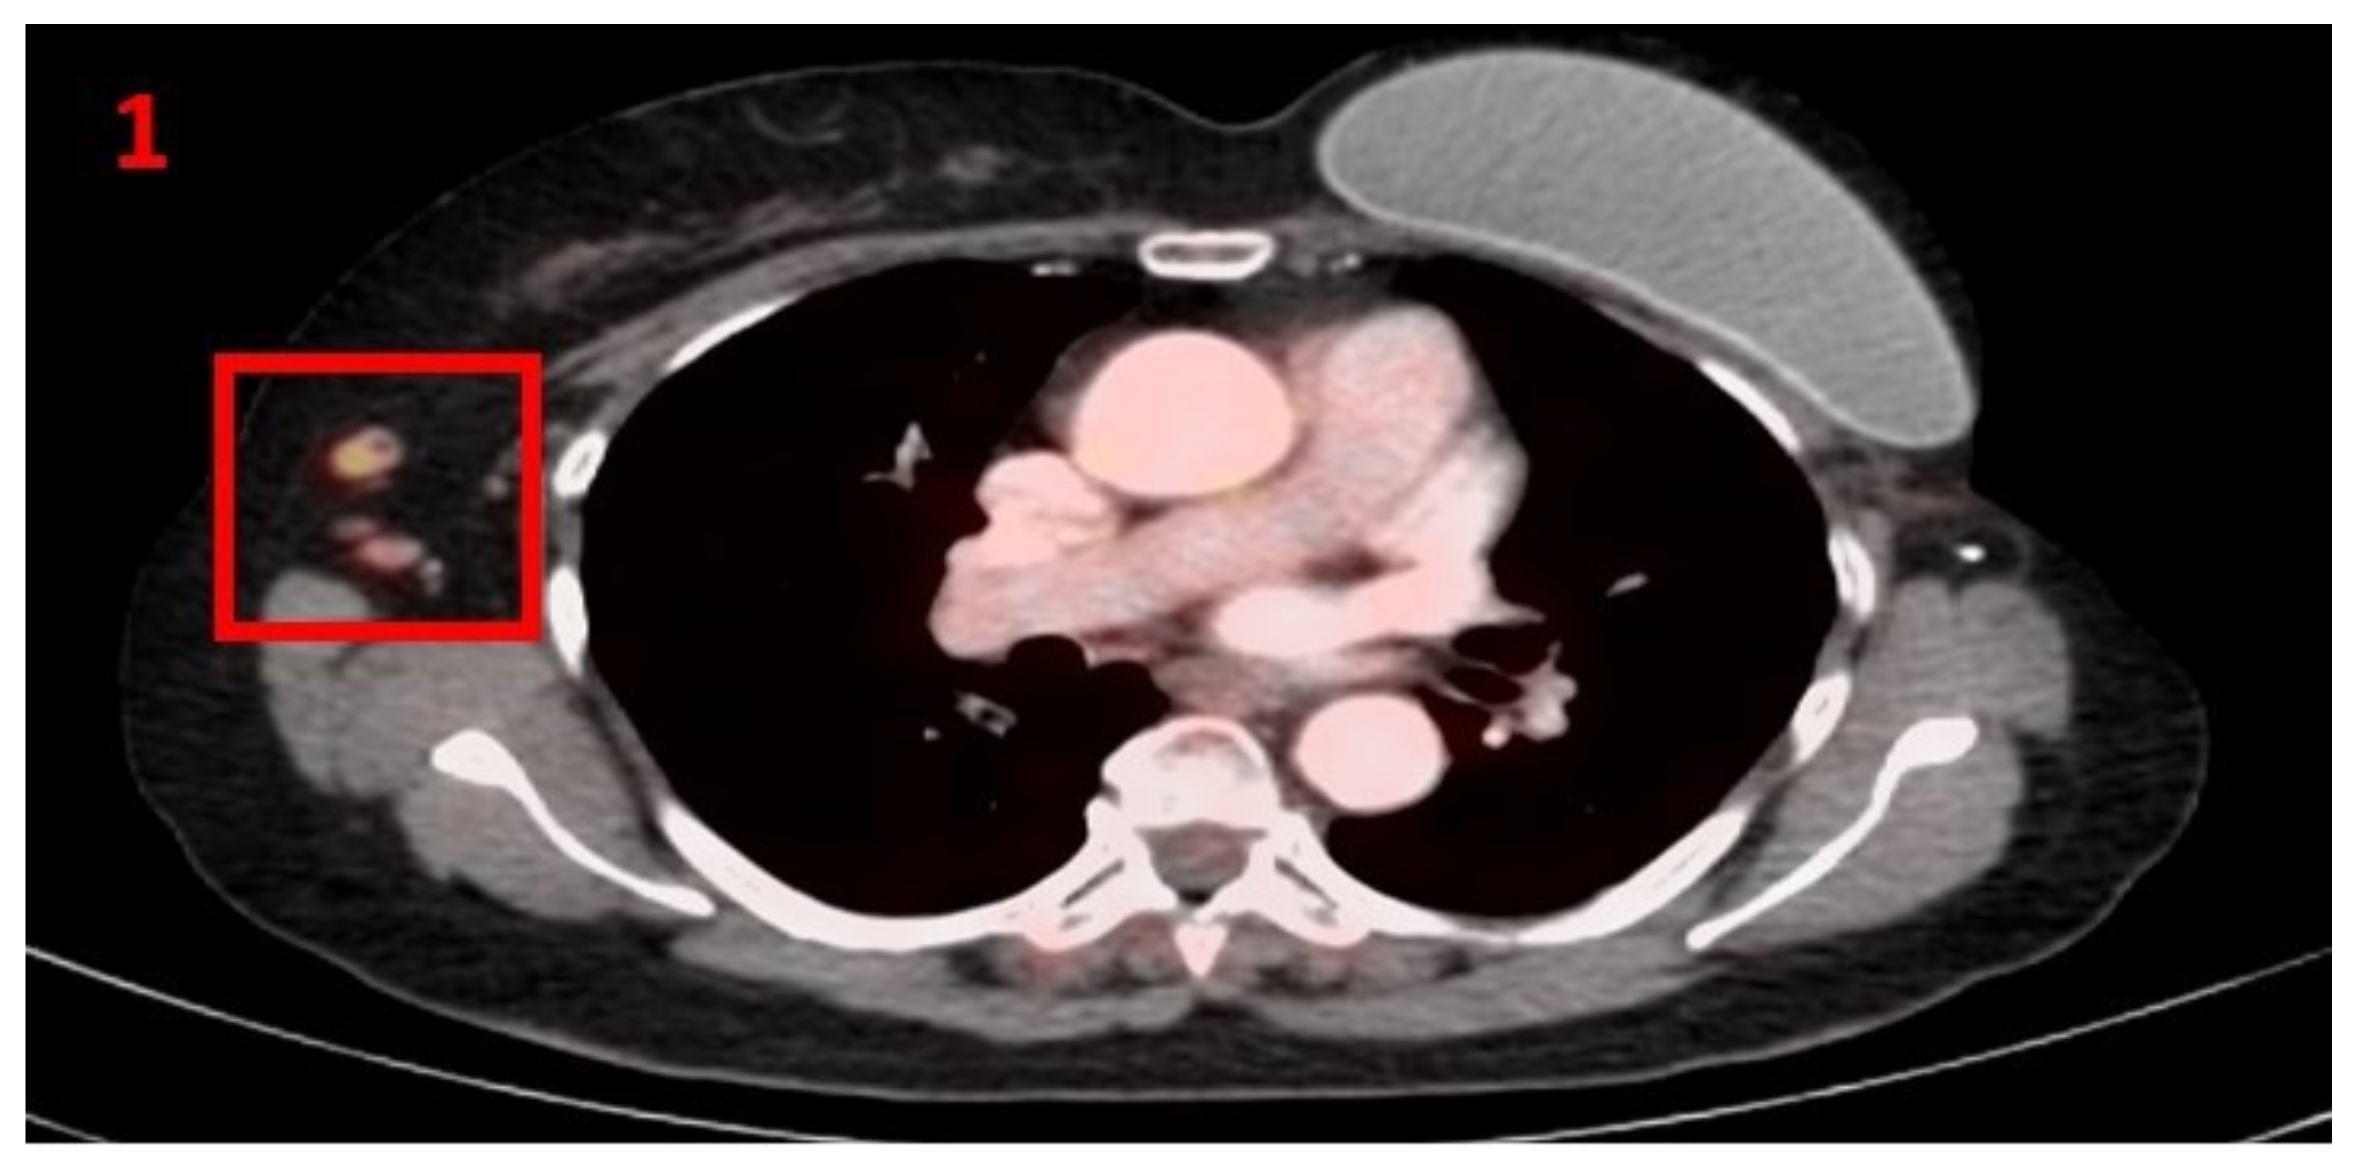

3.1. Case No 1

| Case no.1 | Breast cancer | Right arm | 5 days | Hypermetabolic uptake in the right axillary region and lymphadenopathy | First vaccine | 10 mm | 4.6 | Pfizer-BioNTech |